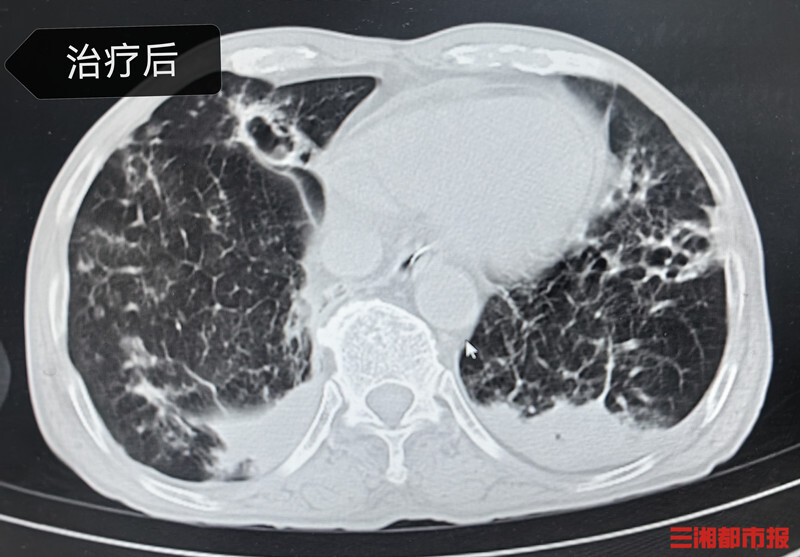

通过治疗,姚大爷最终转危为安。一段时间后续治疗后,2月5日,姚大爷身体达到出院条件,待雨雪冰冻天气情况好转后返乡过年。